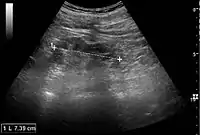

Ultrasound findings that indicate pyelonephritis are enlargement of the kidney, edema in the renal sinus or parenchyma, bleeding, loss of corticomedullary differentiation, abscess formation, or an areas of poor blood flow on doppler ultrasound.[21] However, ultrasound findings are seen in only 20% to 24% of people with pyelonephritis.[21]

Chronic pyelonephritis with reduced kidney size and focal cortical thinning. Measurement of kidney length on the US image is illustrated by ‘+’ and a dashed line.[20]